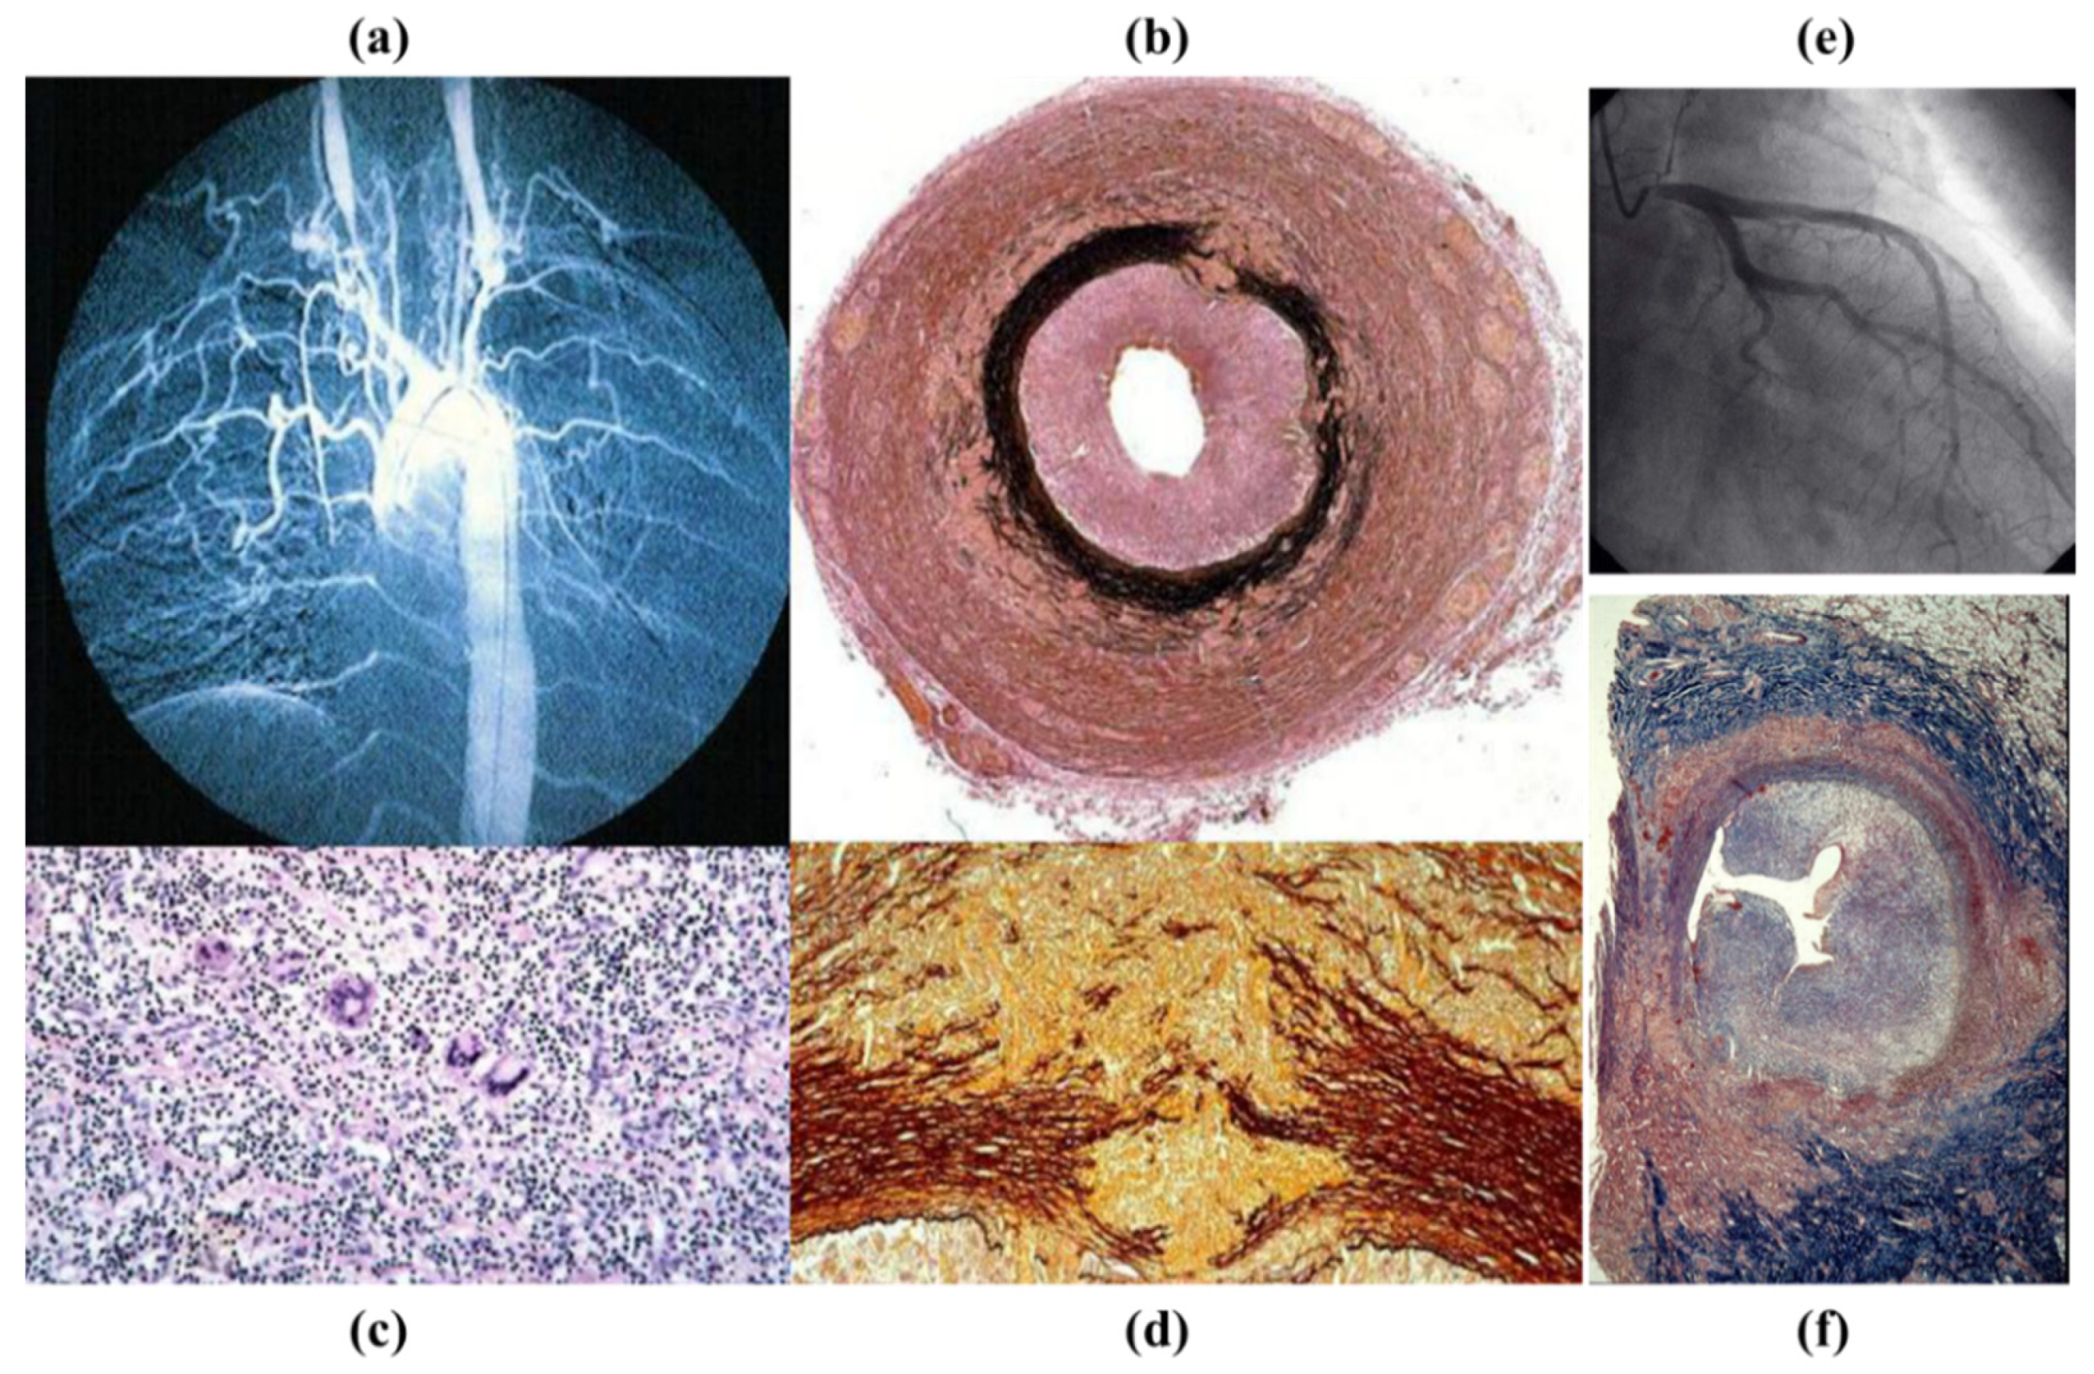

2. Normal Anatomy

3.3. Degenerative Diseases of the Aorta

3.4. Inflammatory Diseases of the Aorta